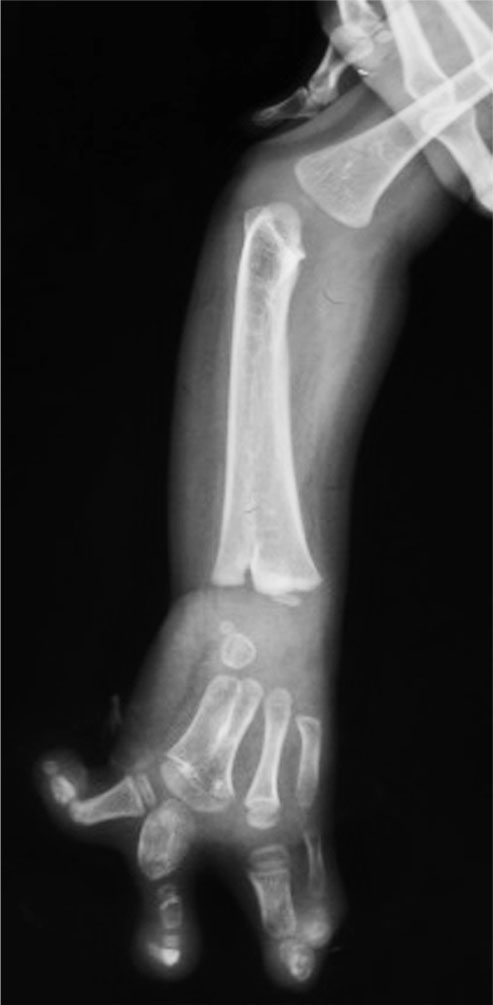

(3)桡骨完全缺如(图1-2-5)。

图1-2-5 桡骨完全缺如病例

A.右侧前臂桡侧纵列发育不良,拇指完全缺如;B.X 线片显示桡骨完全缺如,腕关节极度桡偏、脱位